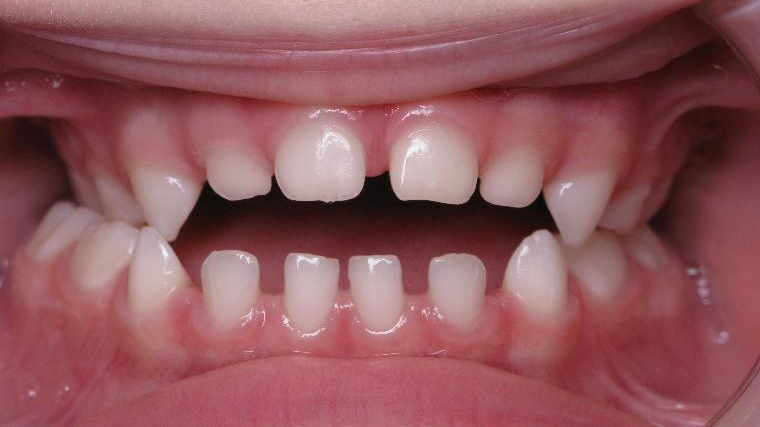

inversion postérieur coté droit et espace entre les dents du haut et du bas (diastèmes)

bilan début et en cours de traitement